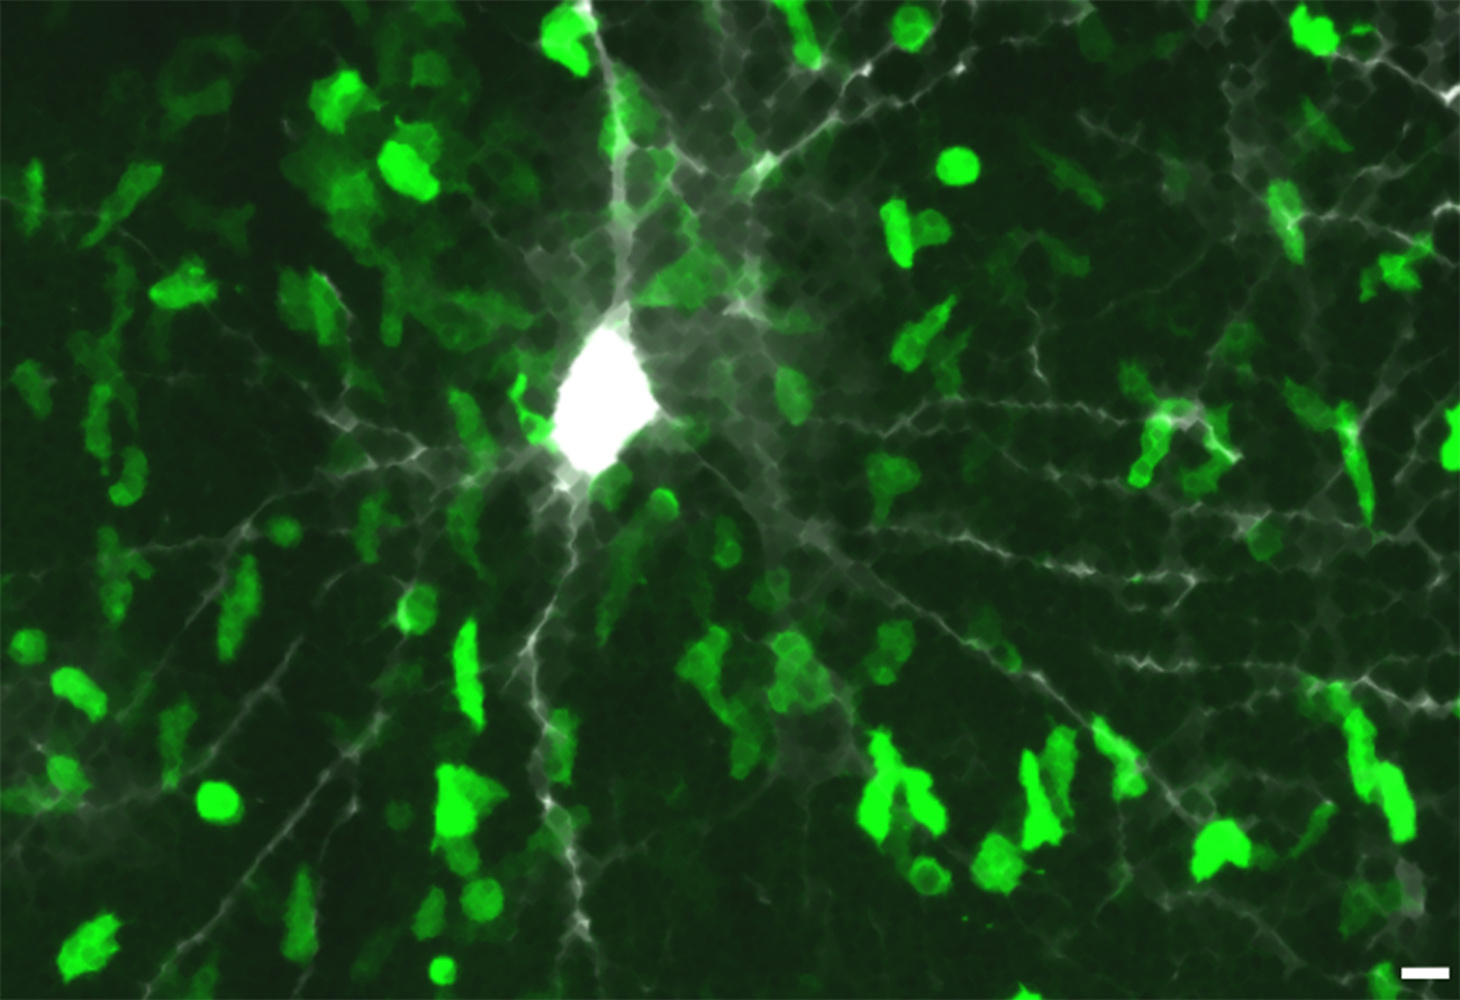

BILDUNTERSCHRIFT: Abbildung: Beta-Synuclein-erkennende T-Zellen stürmen die graue Hirnsubstanz. Zu sehen ist eine mikroskopische Aufnahme in der Hirnrinde einer Ratte. Die pathogenen T-Zellen (grün) sind in großer Zahl in das Gewebe der grauen Hirnsubstanz eingedrungen. Zum Teil bilden sie direkte Kontakte mit einer Nervenzelle und deren Fortsätzen (grau-weiß). Vergrößerungsbalken: 10µm. Bild: Institut für Neuroimmunologie und Multiple-Sklerose-Forschung